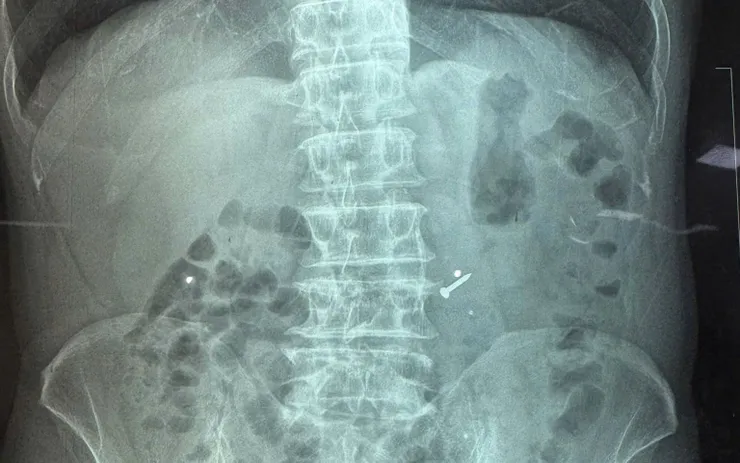

Tại đây, bệnh nhân được thăm khám khẩn trương và chụp phim xác định vị trí dị vật. Nhận định nguy cơ cao gây tổn thương thực quản, dạ dày hoặc ruột, Khoa Cấp cứu đã phối hợp với Khoa Nội soi Tiêu hóa tiến hành can thiệp.